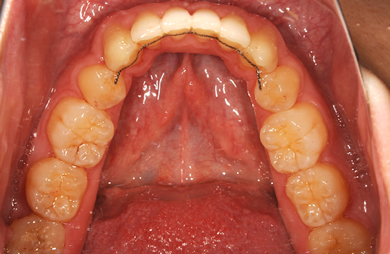

矯正の症例写真 ORTHODONT

全顎矯正治療

| 主訴 | 乱ぐい歯を治したい。 | ||||||||||||||||||||||||||||||||

| 治療方針 | 歯のがたつきが大きいことより上下左右第一小臼歯を抜歯して、マルチブラケット装置にて治療。また、親不知がまっすぐ生えることができず横を向いている状態なので、まっすぐにする隙間があることから親不知も使用し、矯正を行う。 | ||||||||||||||||||||||||||||||||

| 治療内容 | 唇側矯正(ホワイト) | ||||||||||||||||||||||||||||||||

| 総治療費 | 663,810円 | ||||||||||||||||||||||||||||||||

| 治療期間 | 2ヶ月 |